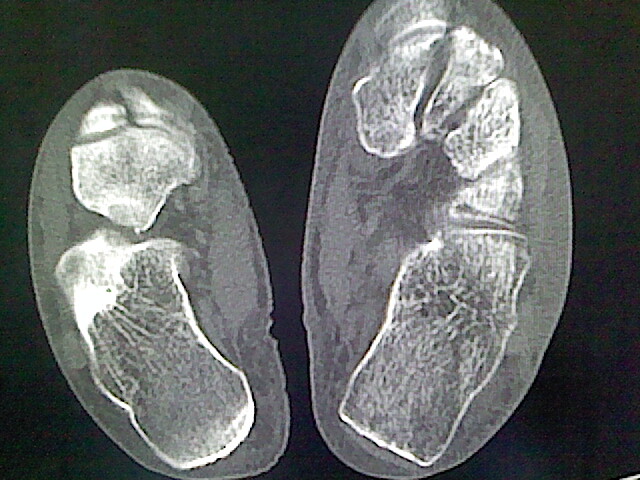

标题: CT16814:男,76岁,左小腿疼痛,不能站立 大家给看看 [打印本页]

男,76岁,左小腿疼痛,不能站立

本例骨质改变主要表现为滑膜或韧带区的骨侵蚀融解(胫腓联合区骨质破坏无硬化边),距骨后部骨质破坏区有硬化边及死骨样改变.所以,本例考虑关节结核可能性大,绒毛膜结节性滑膜炎多发于中年,且极少见于膝髋以外的关节,骨质硬坏也以压陷吸收为主,有明显的硬化边,骨膜增生呈结节状(可以mr鉴别),所以本例暂除外.

另不除外可引起相似表现的其他炎症如布氏杆菌性关节炎等